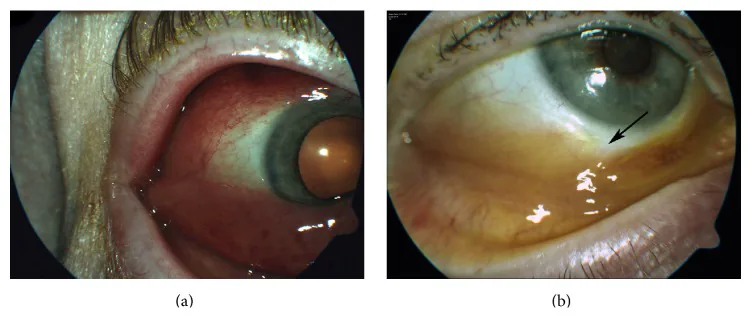

瘢痕性眼瞼外反:慢性炎症と退行性変化による前葉の瘢痕化。下眼瞼縁が外側に反転する。SSを示唆する所見である。

瘢痕性眼瞼外反:慢性炎症と退行性変化による前葉の瘢痕化。下眼瞼縁が外側に反転する。SSを示唆する所見である。

初期CTCL患者では眼瞼病変が良性皮膚炎を模倣することがある。CTCLは過去の外傷や手術瘢痕部位に局在する傾向が報告されており、瘢痕を悪化させ外反を招く可能性がある。

眼瞼への悪性T細胞の浸潤が慢性炎症を惹起し、脂漏性眼瞼結膜炎やマイボーム腺炎を引き起こす。慢性炎症による前葉の瘢痕化・退行性変化が瘢痕性外反の原因となる。

CTCLは過去の外傷・手術瘢痕部位に局在する傾向が報告されており、既存の瘢痕を悪化させ外反を助長する可能性がある。睫毛脱落は眼瞼縁の腫瘍浸潤または高度炎症による毛包破壊を反映する。